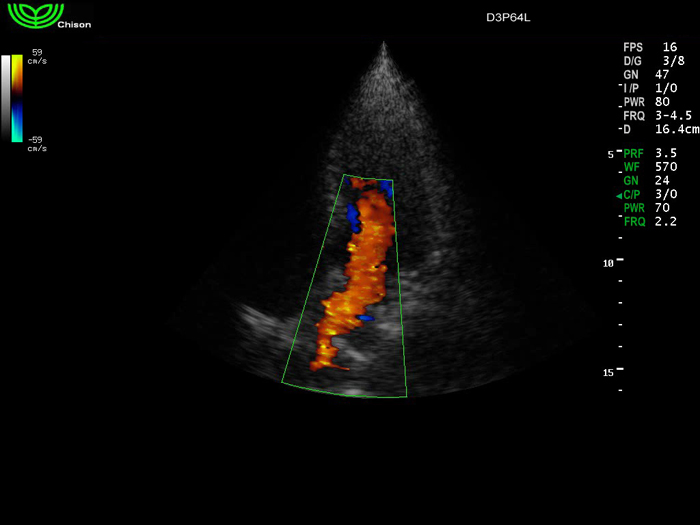

D3P64L 3.0МГц, фазированная решетка.

2.0МГц – 4.4МГц. Применения: кардиология, брюшная полость, акушерство. |